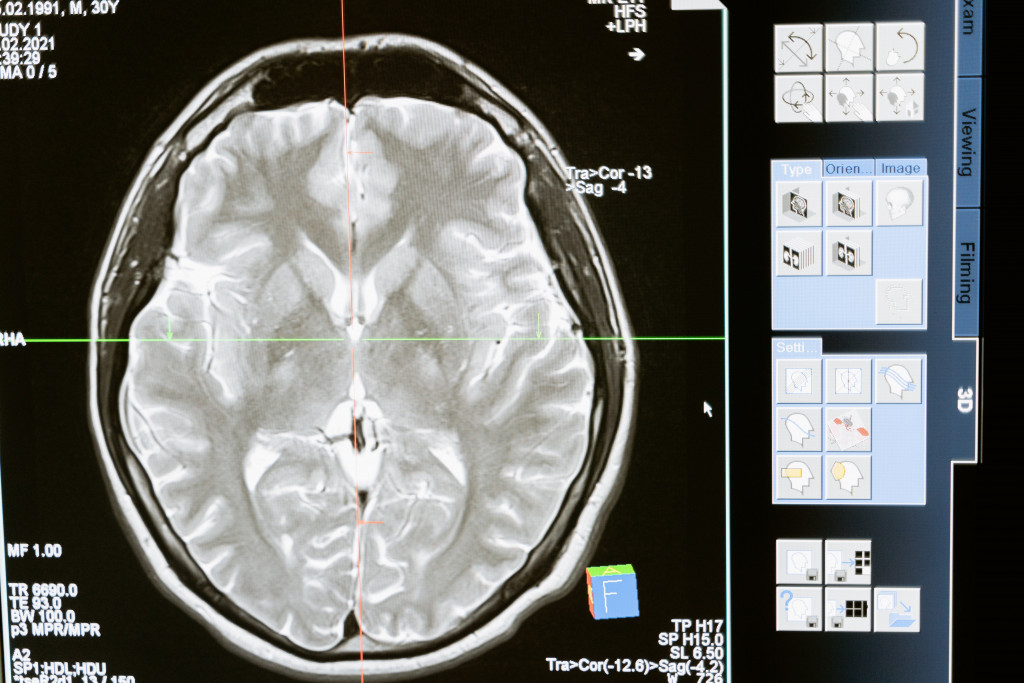

Nakon što je primetio da dnevno pije 10 litara vode, obratio se lekarima koji su odmah posumnjali da ima dijabetes. Uradio je potrebne analize, ali rezultati su pokazali da ne boluje od dijabetesa, već da se iza njegove ekstremne žeđi krije tumor mozga koji je smešten u hipofizi - maloj endokrinoj žlezdi, prečnika do 15 milimetara, koja se nalazi u koštanoj duplji lobanje, ispod mozga.

Deo mozga veličine graška kontroliše osećaj žeđi, a u Plamerovom slučaju, terao ga je da pije pet puta više od preporučene dnevne doze. Tek kad je otišao na rutinski pregled vida, uočena je izraslina i upućen je u bolnicu na magnetnu rezonancu kojom je otkriveno da ima tumor na mozgu. Džonatan, koji je inače poštar iz Falmouta u Kornvelu, prošao je 30 ciklusa zračenja i sad više nema tumor.